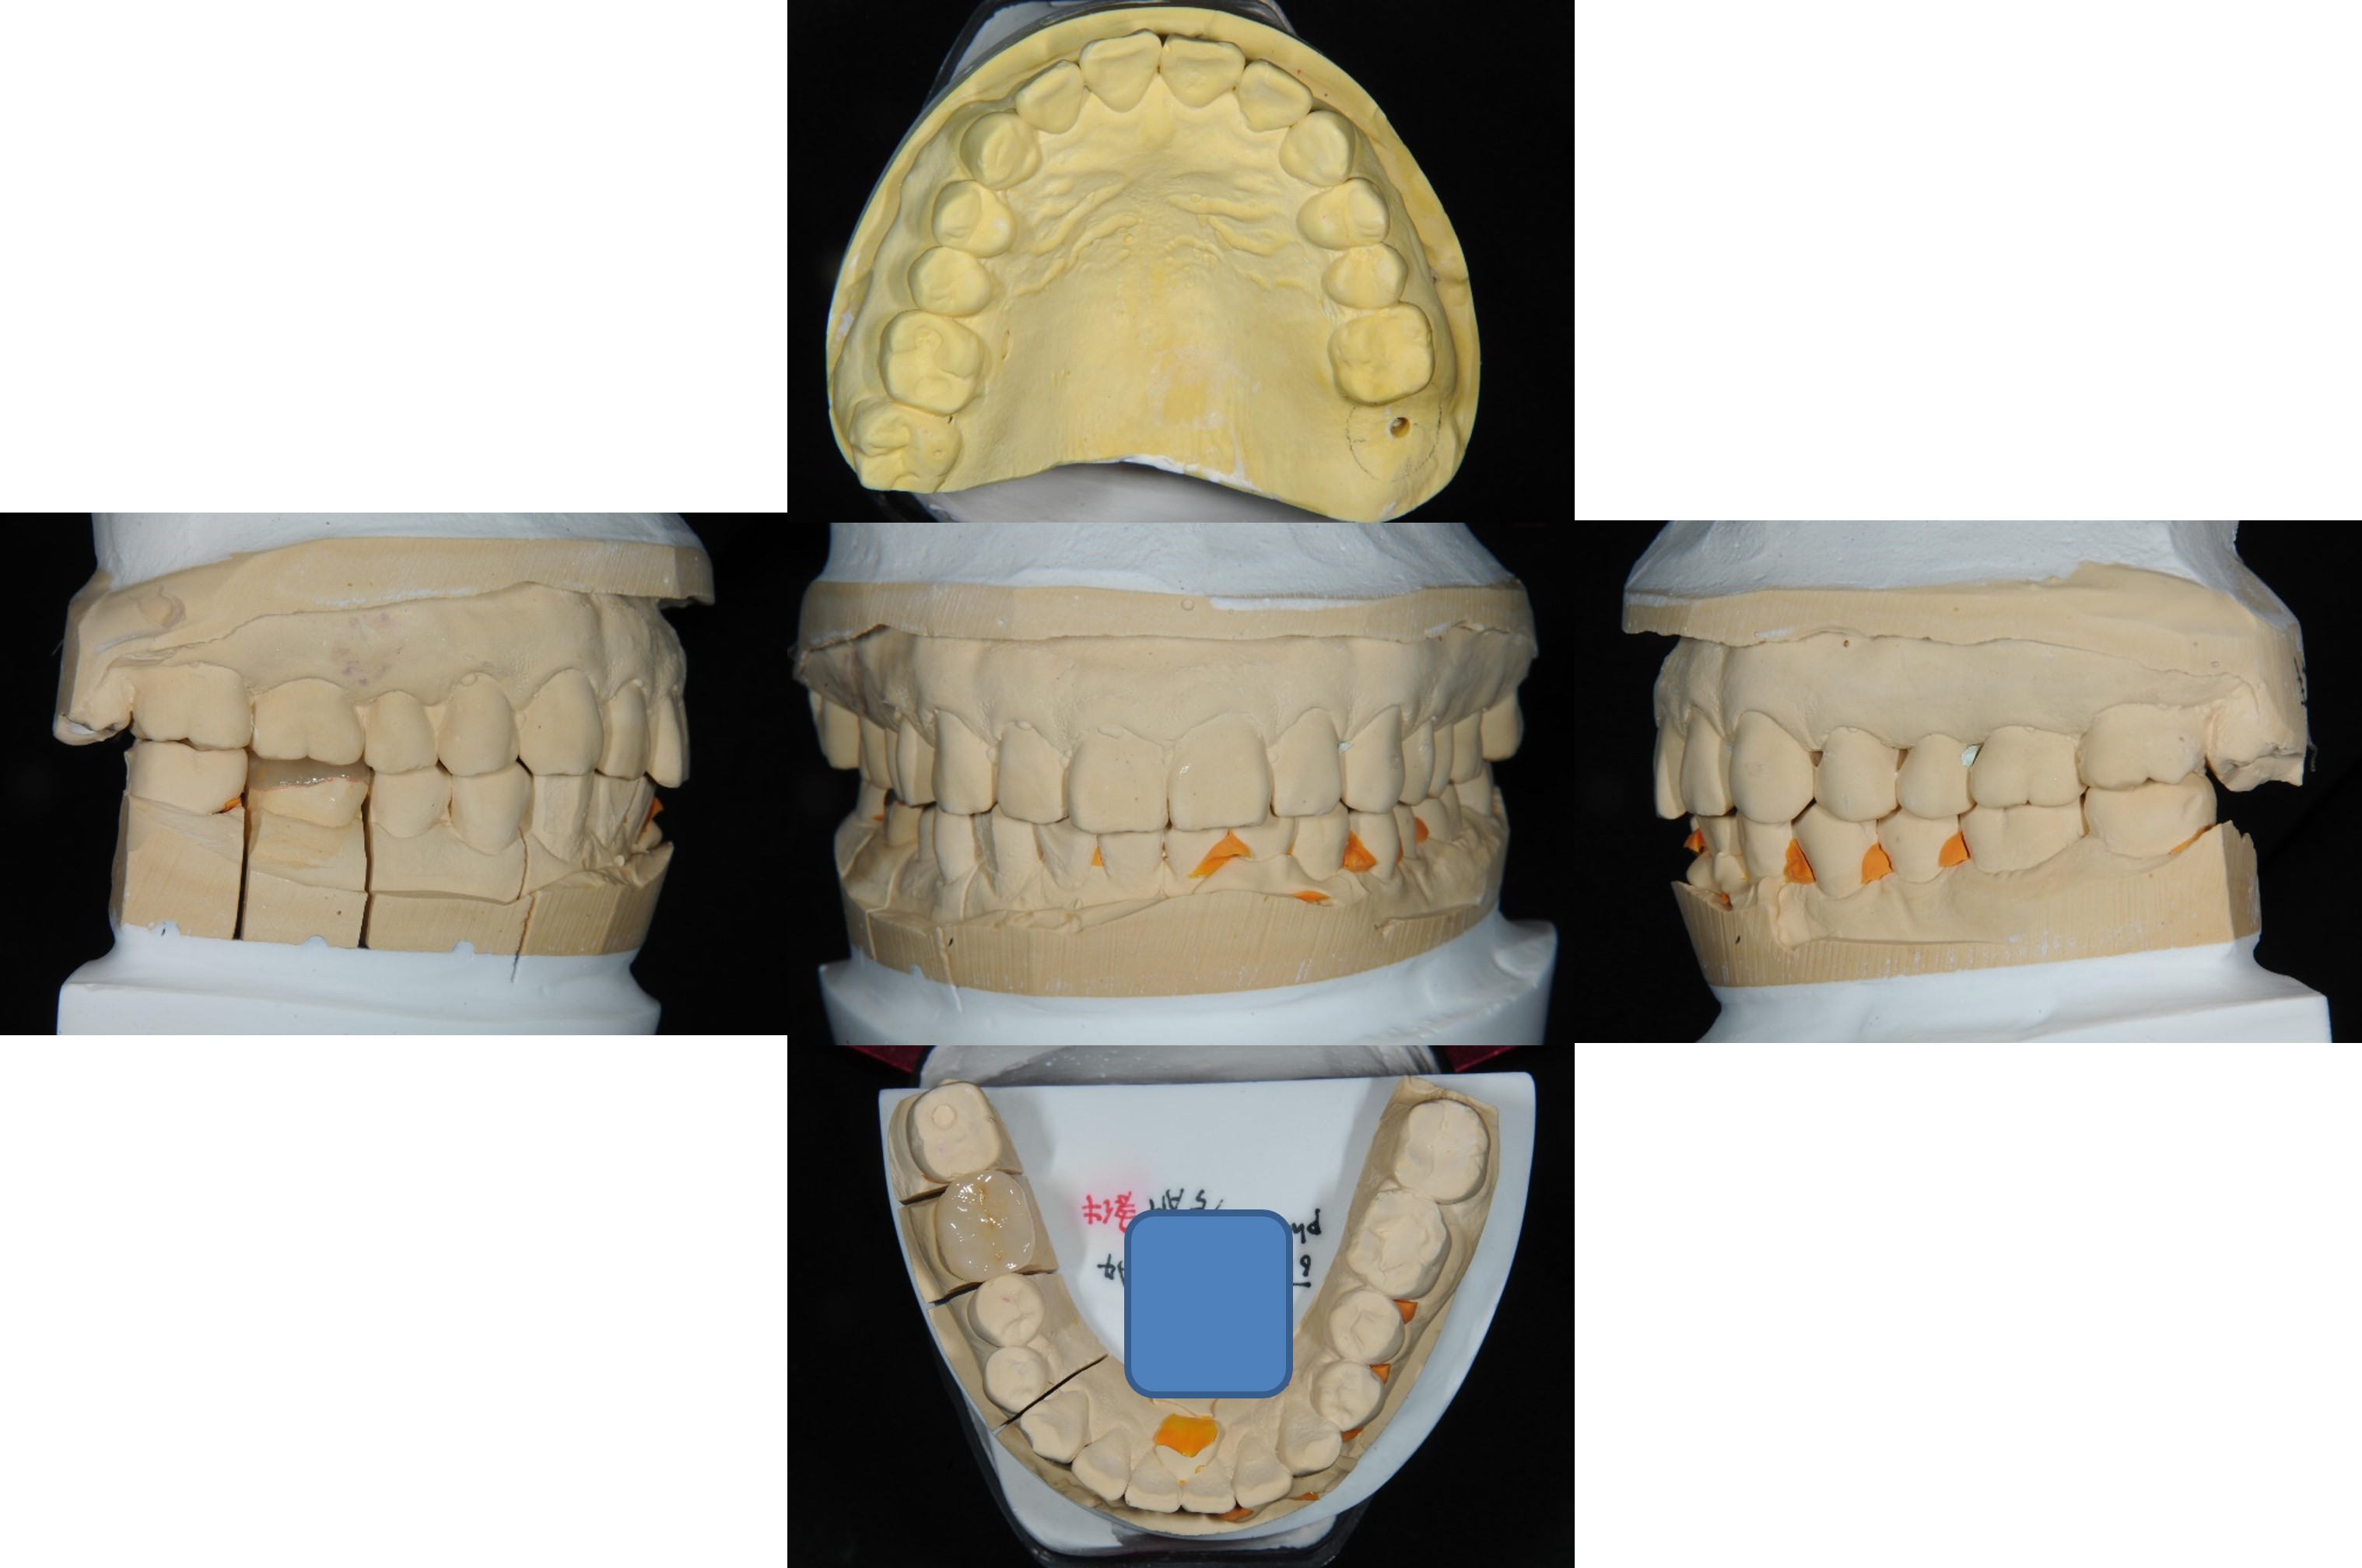

上面弓,咬合器

陶瓷冠塊體製作